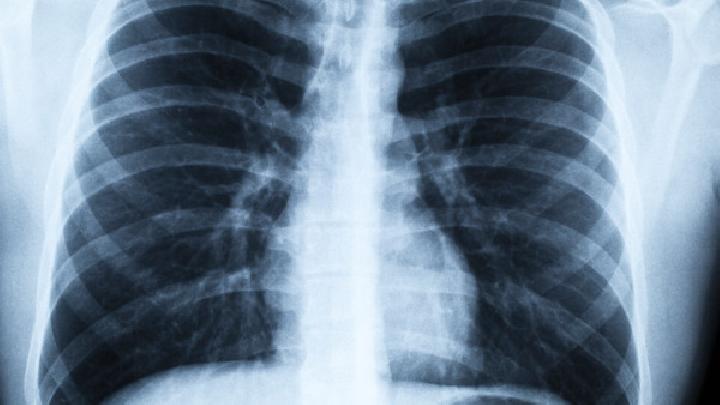

肺炎,是指肺部的肺泡出现发炎的症状,病程超过3个月者为慢性肺炎。慢性肺炎的患者,在选择治疗方法的时候一定要注意听医嘱,不同的病人治疗方法是不一样的。另外,慢性肺炎患者在平时应适宜锻炼,增强自身体质。

长期活动量不足,会使运动耐力下降,呼吸功能障碍更加明显,形成恶性循环。适度的运动训练可以提高肌肉的血流量和氧利用率,提高呼吸肌的运动功能和耐力,从而改善症状。对不同的患者,应制定不同的训练计划,选择合适的锻炼方法和强度,循序渐进。根据美国运动医学学院(ACSM)的指导,在全身运动时,运动强度达预计最高心率的60%~90%,持续20~45min,每周3~5次。

但是,患者不宜做剧烈运动。因为人运动是主要是调动人体的心肺功能,肺主要是给将吸入的氧气供给血液的。如果肺不好的话,就要一开始慢慢来,然后加大呼吸,每次锻炼的时候给自己一点点挑战,强度不要过大,循序渐进的提高自己的心肺功能。可以做有氧运动。有氧运动好可以起到缓解症状提高身体免疫力治疗慢性疾病的作用。